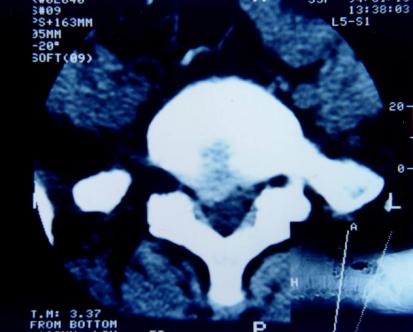

CT检查:具有确诊价值。将人体的脊柱的通过CT扫描仪,各个平面扫下来,总能看到你想要看到的层面,但CT只能看到密度较高的东西,如骨头、骨质,而对于神经等相对“软”的东西,敏感性不佳。

磁共振检查:跟CT一样,具有确诊价值,同时由于其成像原理,对于观察神经以及是否存在神经压迫水肿信号,有独特的优势,也是目前诊断腰椎间盘突出,明确神经压迫的主要检查,老百姓没学过医的也可以看得到的“突出”!